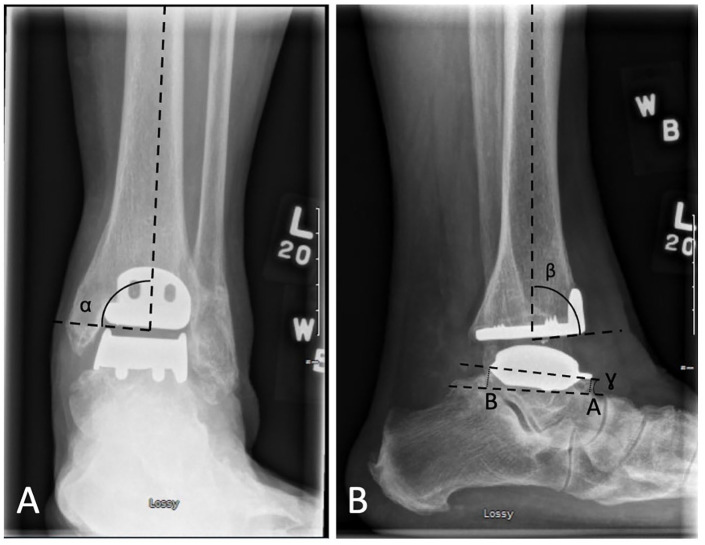

Methods: Retrospective study including all HINTEGRA TARs completed by 1 experienced foot and ankle surgeon from 2006 to 2014. Radiographs were reviewed, assessing for implant positioning, presence, location, and progression of cysts as well as relationship between osteolysis with reoperations and revisions.

Results: Fifty-one TARs were identified with radiographic follow-up of 5.8 ± 3.5 years. Eighty-four cysts were detected in 37 patients, with increasing number and size of cysts being correlated to length of time from surgery. The most common location was the posterior tibia. Thirteen patients had enlarging cysts identified over time, with the lateral malleolus being the most common location. Seven patients met criteria for malaligned prosthesis, 12 patients required a reoperation, and 2 patients experienced implant failure.